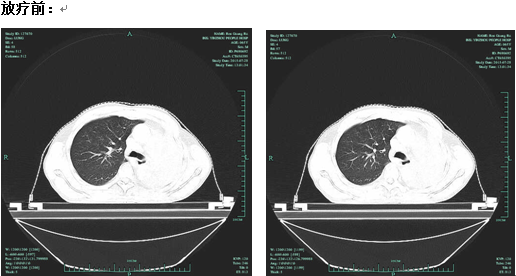

(以下为放疗前后对照CT)

56岁的李先生是个老烟枪,一天得抽3包烟,只要醒着就要抽烟,听他老婆讲,他把家里的蚊帐都熏黄了。一个月前,李先生出现了咳嗽咳痰、胸闷气急不适,以为是感冒就到社区卫生服务站打了几天消炎针,结果不但没好,反而原来越严重。家人赶紧把他送到了鄞州人民医院,经过检查后发现李先生得了肺癌。肿瘤长在左侧肺门处,因为空气无法从肺门进入肺部,从胸片上可以发现李先生的左肺像憋了气的气球,完全失去了肺的通气功能,由于左肺基本不张,所有的通气功能都要右肺承担,右肺透亮饱满,不堪重负。

立体定向三维调强放射治疗技术是精确放疗的一种治疗方式,它与常规的放射治疗相比,该技术需要医生付出更多的精力,更多的耐心和细心。徐正阳主任团队利用CT、MRI、X光片等影像技术,借助计算机的特殊软件反复对照,终于得到了病变在体内的精确空间位置。不仅如此,他们还为李先生认真反复计算,得出了控制肿瘤所需的精确的放射靶区剂量和次数,目的是使立体定向三维调强放射治疗技术能精确照射,从而帮助李先生杀灭肺门的肿瘤,提高他的生活质量。李先生自9月8号第一次采用放疗治疗至今,不仅没有出现放射性肺炎等严重并发症,而且病灶减小,左肺又重新张开了,心脏功能也恢复了正常。